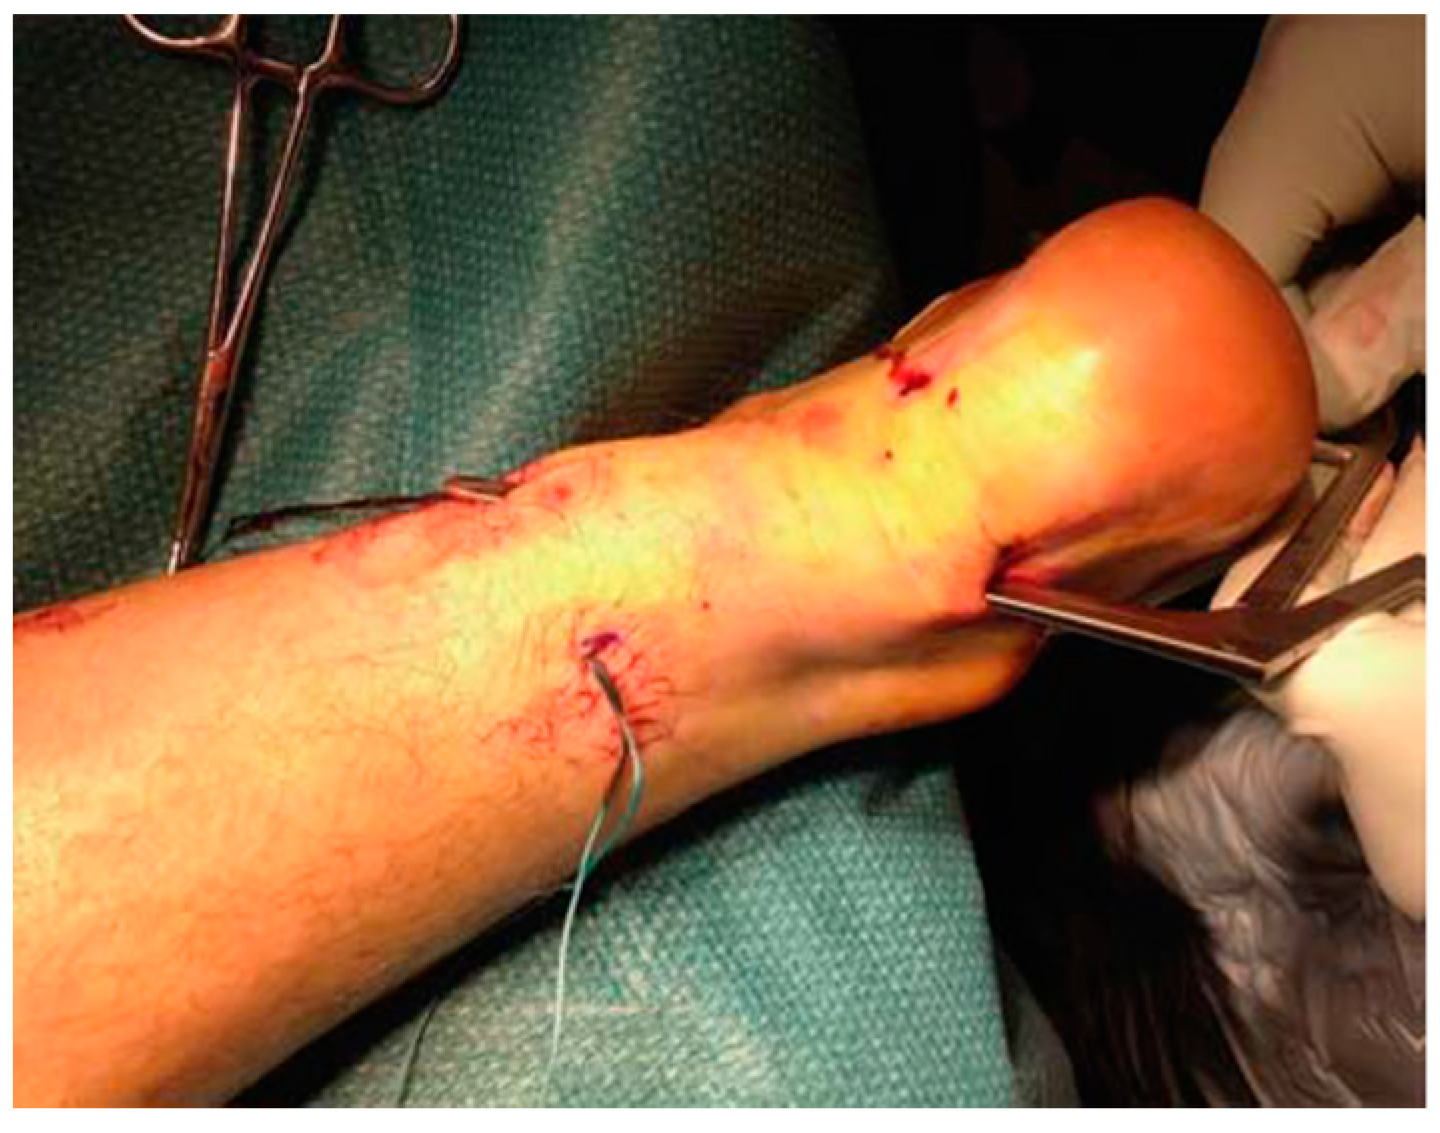

3.4.2. Minimally Invasive Techniques for AT

- Maffulli, N.; Oliva, F.; Maffulli, G.D.; Giai Via, A.; Gougoulias, N. Minimally Invasive Achilles Tendon Stripping for the Management of Tendinopathy of the Main Body of the Achilles Tendon. J. Foot Ankle Surg. Off. Publ. Am. Coll. Foot Ankle Surg. 2017, 56, 938–942. [Google Scholar] [CrossRef]

- Maffulli, N.; Testa, V.; Capasso, G.; Bifulco, G.; Binfield, P.M. Results of Percutaneous Longitudinal Tenotomy for Achilles Tendinopathy in Middle- and Long-Distance Runners. Am. J. Sports Med. 1997, 25, 835–840. [Google Scholar] [CrossRef]